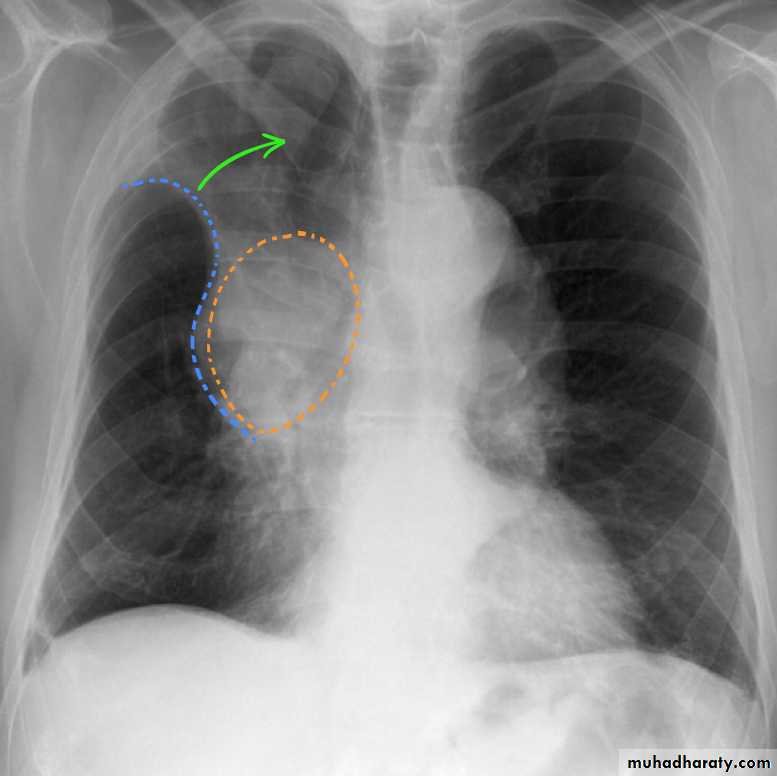

Golden S sign collapse with RT ULC

41.RT UL collapse

42.RT UL collapse

43.golden S sign